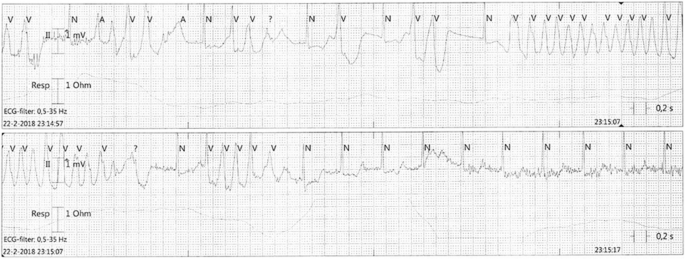

That night, 36 h after admission, our patient developed recurrent short episodes of Torsades de Pointes (TdP) with intermittent loss of cardiac output, as shown in Fig. 2. Two grams of magnesium sulphate was administered intravenously, after which sinus rhythm was restored. Four hours later, she had complete loss of circulation, after which cardiopulmonary resuscitation was initiated according to protocol. A 150-J biphasic shock was delivered using an automated external defibrillator (Zoll R-Series ALS). ECG findings consistent with TdP were again observed. Spontaneous circulation was restored after intravenous administration of magnesium sulphate. Our patient was awake and immediately able to maintain a patent airway following the incident. Serum levels of fluoxetine and risperidone and their metabolites were measured in retrospect, as shown in Table 1 and Fig. 3a, b. Laboratory findings at the time of the incident showed a mild hypocalcaemia of 2.10 mmol/l with a hypermagnesaemia of 1.72 mmol/l/, most likely caused due to the prior administration of magnesium sulphate. No other electrolyte abnormalities were identified (Na+ 137 mmol/l, K+ 3.8 mmol/l, PO43− 1.24 mmol/l). Subsequent ECGs showed progressive prolongation of the QTc interval up to 565 ms, as shown in Fig. 4. The patient remained hemodynamically stable for the remainder of the night on continuous infusion of magnesium sulphate (1 g/h). The following day, echocardiography was performed in order to exclude structural cardiac defects, which showed normal heart dimensions as well as a normal left and right ventricular function.